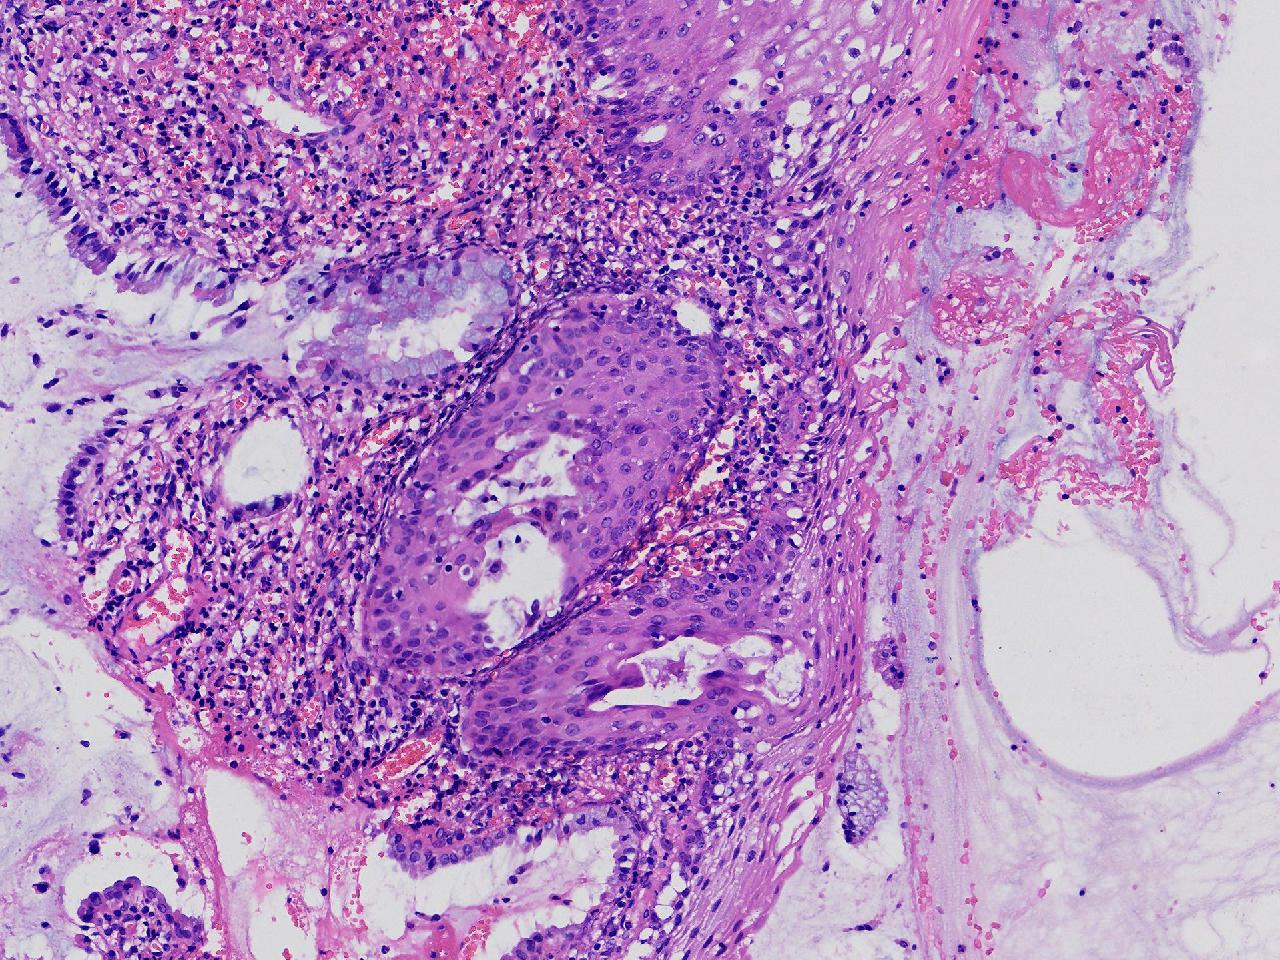

CIN1级? CIN2级?

女,41岁,宫颈活检,HPV16(+)

宫颈多点活检。

灰白色不整形软组织多块。

慢性宫颈炎伴鳞化,建议定期复诊

慢性炎,储备细胞增生伴鳞化,